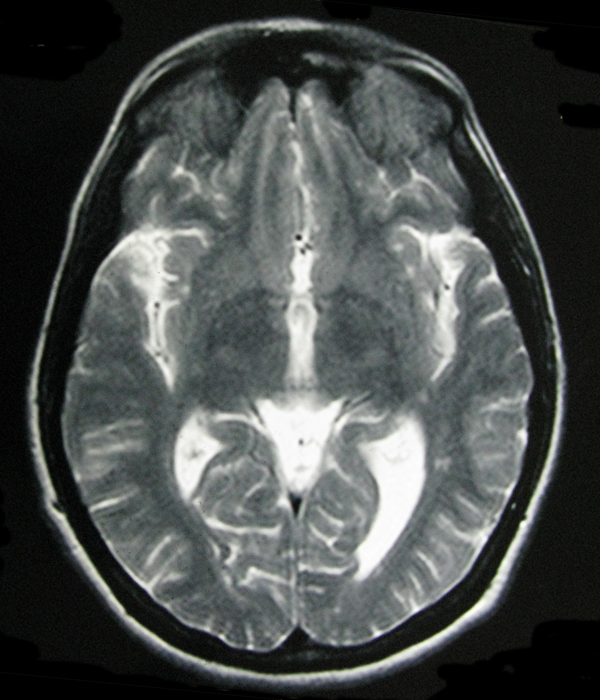

- My Brain in 2009